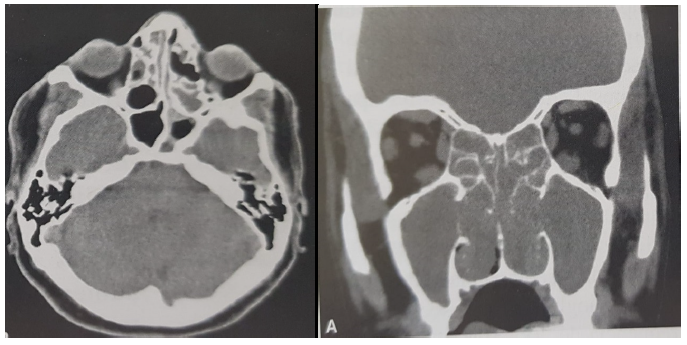

Após realização de rinoscopia, foi solicitada tomografia da face, que resultou na seguinte imagem:

Considerando as informações, escolha a melhor alternativa.